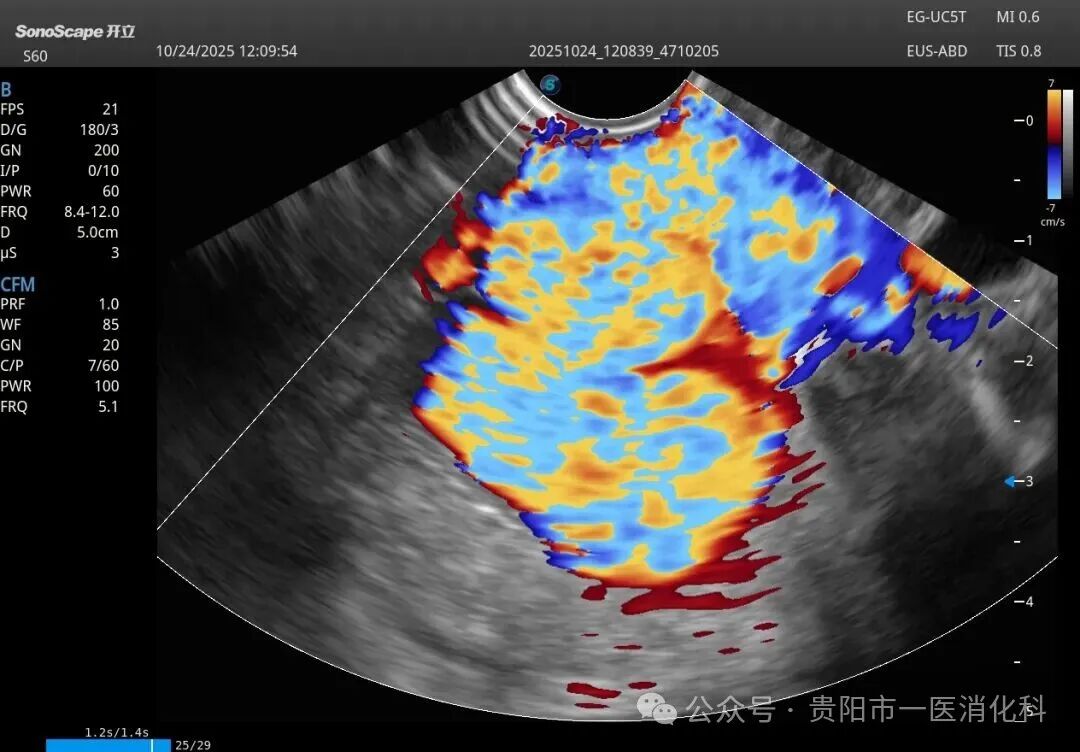

在王俊雄教授的全程指导下,手术如期进行。术中,专家团队首先将超声内镜送达胃底,屏幕上立即清晰显示出曲张静脉的横断面、深度、血流以及其来源血管。在超声的“火眼金睛”引导下,穿刺针犹如被安装了“GPS导航”,精准刺入目标血管。随后,医生们先将数个微弹簧圈送入血管内,构建一个坚实的“巢”,再注入医用组织胶水。弹簧圈与组织胶迅速结合,形成稳固的复合栓塞物,彻底封堵了致命的曲张静脉。整个手术过程流畅,术后患者生命体征平稳,安返病房。